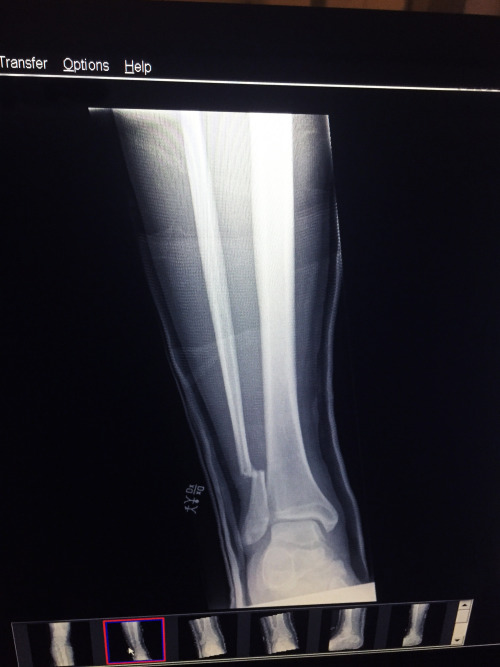

Luego, directo al hospital para radiografías, donde finalmente vimos la magnitud de los daños. Fue entonces cuando las cosas se pusieron realmente reales. Me dijeron que necesitaba cirugía para reparar la fractura. Decidí volar de regreso a Londres y encontrar un médico que pudiera verme lo antes posible. (¡Gracias por la recomendación, Paul!) Una resonancia magnética y unas radiografías, fijó una fecha y prepararon la operación.

Así que ... aquí estoy, recuperándome con 6 tornillos de metal en mi pierna, pensando en la vida y en la TSA de aquí a Kalamazoo ... demonios.